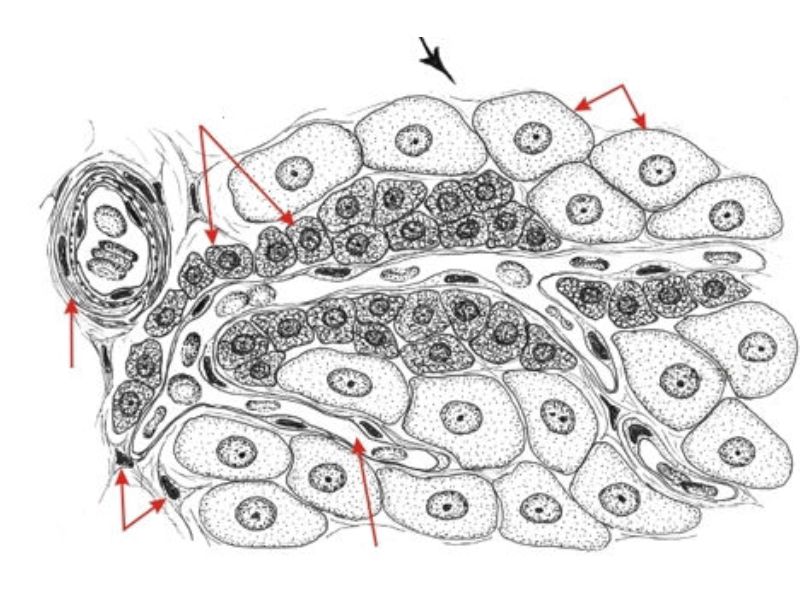

Corpus luteum

Corpus luteum

- Two major cell types

- Granulosa lutein cells

- modified granulosa cells

- Theca lutein cells

- modified theca interna cells

- Many capillaries

Granulosa lutein cells

- Modified granulosa cells

- Large - 30µm

- Pale cells

Theca lutein cells

- Modified theca interna cells

- Smaller - 15µm

- Dark stained